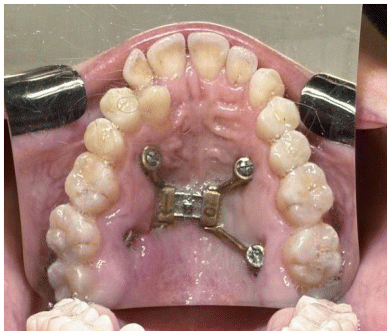

A customized palatal expander has been manufactured utilizing additive manufacturing techniques. It comprises a region containing an expansion screw and fixation arms anchored to the palatal bone, as well as a dental guide that was removed following stabilization to ensure the accurate positioning of the device.

It is advisable to utilize the largest feasible expander screw size, maintaining a 1mm distance from the palatal mucosa and alveolar walls. Expansion screws with standardized dimensions (6, 9, or 11 mm) or adjustable devices are also available. The adjustable extensions facilitate positioning the miniscrews nearer to the palatal surface, which is especially advantageous for patients with severe maxillary atresia (13).

The expander screw should be positioned anteroposteriorly within the palate region that offers optimal conditions for miniscrew placement, specifically areas with adequate bone volume and cortical density. Haas Junior et al. (11) recommended the “T-zone” (14), a notably advantageous site for miniscrew placement, which is generally situated near the midpalatal suture and surrounding the third palatal rugae, where the bone quality is most appropriate for secure anchorage.